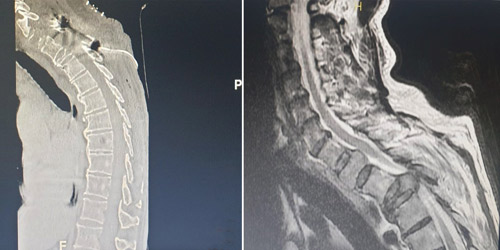

وقال د. مسعود إن المريض كان يعاني أيضاً من آلام حادة جداً أسفل الرقبة وأعلى الفقرات الصدرية، وفور وصوله إلى المستشفى خضع لفحوصات متنوعة ودقيقة، وقد بينت الصور الطبية إصابته بغضروف كبير مع ورم في الفقرة الصدرية الثالثة، تسبب في كسر الفقرة، وإحداث ضغط قوي على النخاع الشوكي مما أدى إلى تورمه في منطقة الفقرات العنقية، والفقرات الصدرية، وهذه المعطيات الطبية مجتمعة أدت إلى ظهور الأعراض كافة التي عانى منها المريض وأبرزها: عدم القدرة على المشي واستخدام اليدين بصورة طبيعية، وهو الأمر الذي حد كثيراً من ممارسته لحياته اليومية بالشكل الاعتيادي.

واستطرد د. مسعود قائلاً إن الفريق الطبي أخضع ملف الحالة لدراسة معمقة وخلص إلى ضرورة التدخل الجراحي، وتم شرح الخطة العلاجية للمريض وتجهيزه، ومن ثم أجريت له عملية دقيقة ومعقدة استغرقت نحو «4» ساعات، تم فيها إزالة الغضروف بشكل كامل، ومعالجة الكسر وتثبيت العمود الفقري، ما بين الفقرتين الصدريتين الثانية والرابعة بالبراغي والصفائح، مضيفاً أن العملية شهدت استخدام أجهزة طبية حديثة كالميكروسكوب والملاحة الجراحية لتبيان موضع تثبيت الصفائح بدقة، إضافة إلى أن طريقة الدخول لإجراء العملية كانت نادرة، وتمت عبر فتح قناة النخاع الشوكي وعظم الفقرة وكذلك جزء من عظم الفقرة وجزء من ضلع القفص الصدري، وكانت هذه أفضل طريقة دخول لهذه الحالة المعقدة، سيما وأن المنطقة المتضررة من الإصابة تتسم بالكثير من الحساسية، لاتصالها المباشر بالنخاع الشوكي.

وأوضح د. مسعود أن العملية ولله الحمد انتهت إلى ما سعى إليه الفريق الطبي، وحققت نجاحاً كبيراً بفضل الله، وهذا ما أكدته صور الرنين المغناطيسي بعد العملية، كما أن حالة المريض بدأت في التحسن التدريجي عقب خروجه من غرفة العمليات، واستعاد خلال فترة تنويمه التي استمرت لنحو أسبوع القدرة على تحريك أطرافه، إلى أن غادر المستشفى وهو قد تخلص كلياً من الآلام، ويمشي على قدميه مع بعض المساعدة «متكئاً على عصا»، لكن المؤشرات الطبية كافة تؤكد أنه مع العلاج الطبيعي سيستعيد قدرته على المشي بصورة طبيعية.